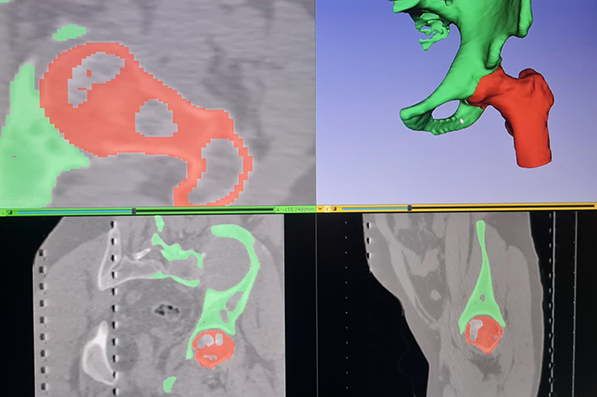

Virtuelni prikaz zgloba kuka pacijenta

Primena trodimenzionalnih (3D) modela, 3D simulacija i 3D štampanja takođe je jedno veliko novo polje, u okviru stalnog naučnog napredovanja u oblasti ortopedske, pa i artroskopske hirurgije. Zahvaljujući primeni kompjuterizovane tomografije (CT) - skenerske tehnologije, omogućeno je digitalno trodimenzionalno modelovanje, odnosno kreiranje 3D modela - virtuelno prikazivanje zglobova - koje istovremeno može da se koristi i za dinamičke simulacije funkcija zgloba. Dinamičko simuliranje funkcija zgloba, uz pomoć 3D virtuelnog prikaza zgloba, često se primenjuje kod postojanja femuroacetabularnog impindžmenta. Na osnovu simulacije može da se predvidi u kojim situacijama dolazi do FAI, na kom mestu i u kom stepenu fleksije kuka, te da se prema tome precizno odredi gde i koliko kosti je neophodno artroskopski obraditi da bi se taj problem rešio.